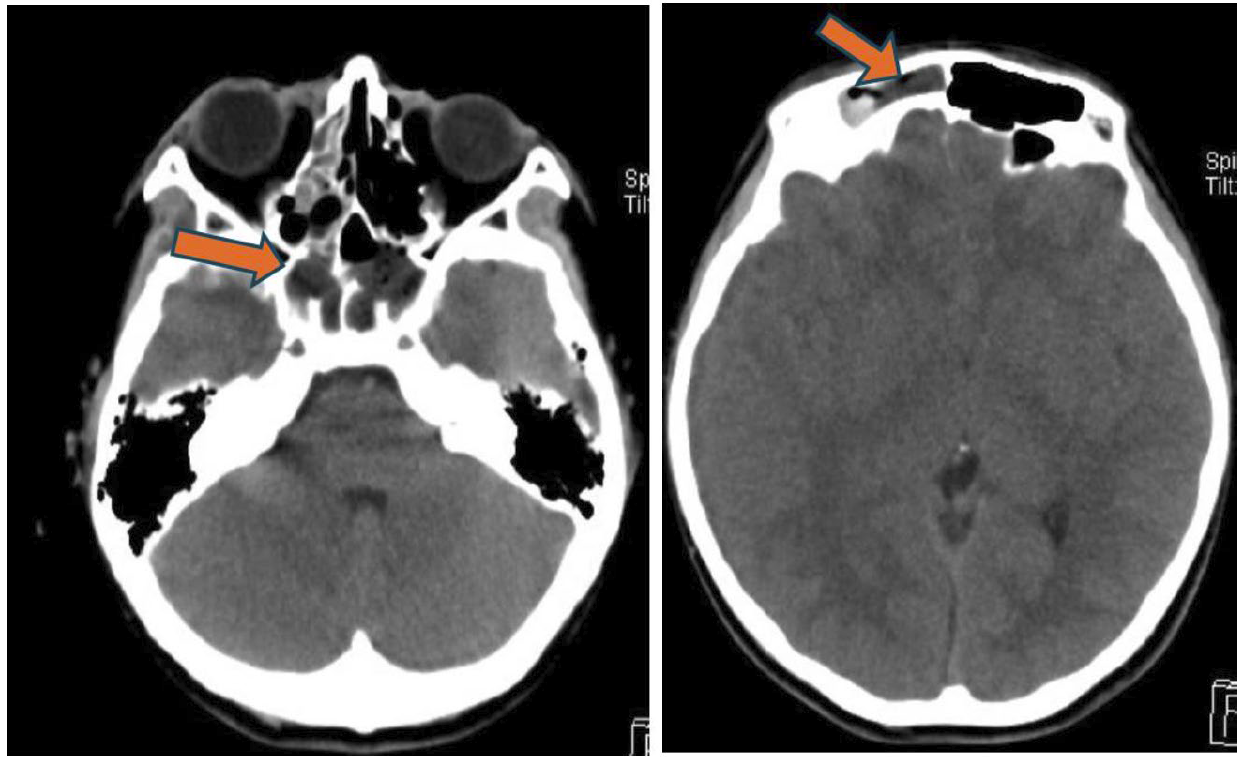

圖二、頭部電腦斷層軸狀切面(axial view):左圖,雙側蝶竇(sphenoid sinus) ,呈現不同密度的充填影像(橘紅色箭頭)。右圖,右側額竇(frontal sinus),呈現不同密度的充填影像(橘紅色箭頭)。

圖四、頭部電腦斷層軸狀切面(axial view)(左圖)和冠狀切面(coronal view)(右圖):硬腦膜附近,呈現一層不均勻密度的積液(橘紅色箭頭)。